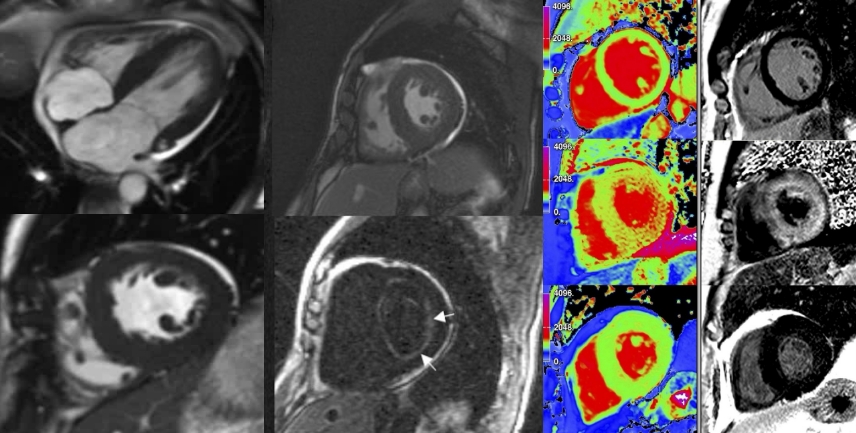

Früherkennung rettet Leben: Mit modernster Diagnostik schaffen wir im Sana Praevention München Schwabing die Grundlage für eine exakte Beurteilung Ihrer Gesundheit. Unser Schwerpunkt liegt auf hochauflösender Bildgebung wie Ganzkörper-MRT und Herz-CT, die auch kleinste Veränderungen sichtbar machen – lange bevor Symptome auftreten. So lassen sich Herz-Kreislauf-Erkrankungen, Tumoren oder andere Risiken frühzeitig erkennen und gezielt behandeln.

Dank der Kombination aus innovativer Medizintechnik, umfassender Laboranalytik und individueller ärztlicher Beratung erhalten Sie ein detailliertes Gesundheitsprofil. Dieses Wissen gibt Ihnen Klarheit und ermöglicht, gemeinsam mit unserem Team präzise Präventionsstrategien zu entwickeln.